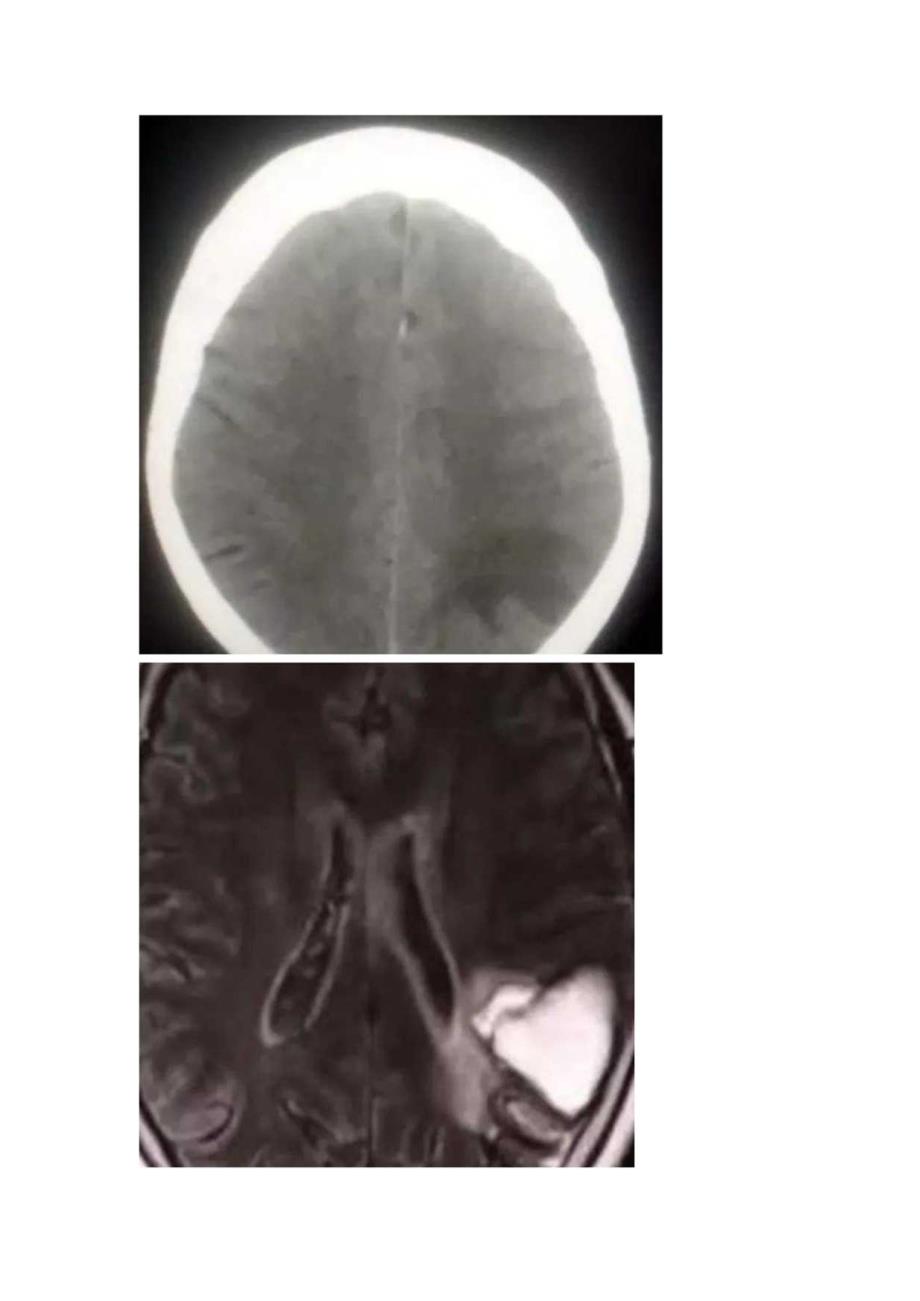

脑淀粉样血管病影像征象